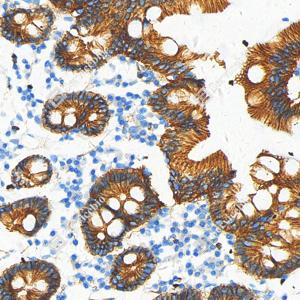

| IHC检测beta Catenin蛋白(货号 GB150016). 样品: 人卵巢癌, 4%多聚甲醛 (货号G1101) 固定12-24小时. 抗原修复: 柠檬酸抗原修复液(干粉, pH 6.0) (G1201), 高压锅均匀喷气计时2分钟. —抗: 1: 500稀释, 4℃ 孵育过夜. 二抗: S-vision免疫组化多聚二抗(山羊抗兔),即用型 (货号G1302), 室温孵育20分钟. |